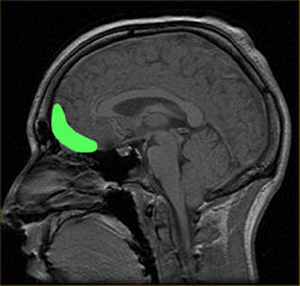

Neuroscientists have discerned at least 10 regions of the brain are involved in what Baron-Cohen calls "the empathy circuit.” One of these is the orbitofrontal cortex. This is a prefrontal cortex region in the frontal lobes of the brain which is involved in the cognitive process of decision-making. The orbitofrontal cortex helps link our rational and emotional brains. Empathy is both a cognitive understanding and an emotional response.

Neuroscientist Kent Kiehl, after scanning the brains of more than 4,000 prison inmates, found structural impairment in areas connecting thoughts and emotions, most notably in the orbitofrontal cortex.